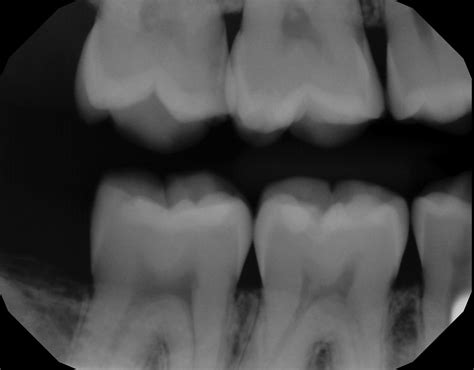

• Between teeth: Also known as interproximal decay, this is one of the most common spots for cavities to form because toothbrush bristles cannot reach these tight spaces.

Not all X-rays are the same, and your dentist will choose the specific type based on your symptoms and oral history. The most common tool for spotting decay is the bitewing X-ray. During this process, you bite down on a specialized piece of film or a sensor, which captures a clear view of the crowns of both your upper and lower teeth on one side of your mouth.

Bitewing Detecting cavities between teeth and checking the height of bone.

When looking at your own X-rays on a monitor, you might find them confusing. Dentists are trained to identify specific visual cues. In a tooth decay X-ray, enamel—the hardest substance in your body—appears as a bright white or light gray area. Healthy bone also shows up in varying shades of white. When tooth decay is present, it appears as a darker, shadowy spot on the image.

This happens because the demineralization caused by bacteria makes the tooth structure less dense, allowing more X-ray radiation to pass through the area. The less dense the tissue, the darker it appears on the radiograph. If your dentist points out a dark spot on your X-ray, they are identifying an area where the mineral content of your tooth has been compromised by acid-producing bacteria.